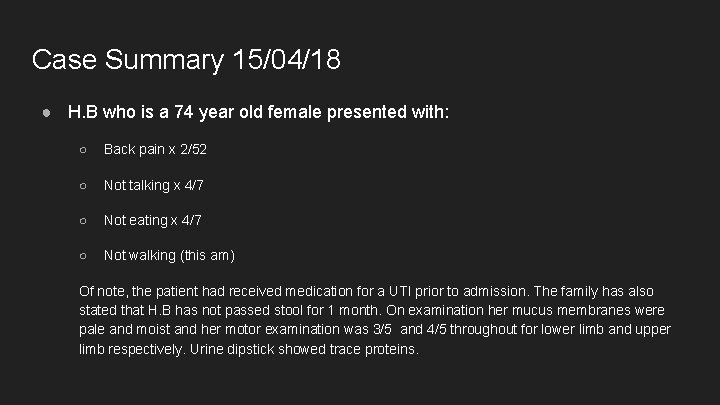

Case Summary 15/04/18 ● H. B who is a 74 year old female presented with: ○ Back pain x 2/52 ○ Not talking x 4/7 ○ Not eating x 4/7 ○ Not walking (this am) Of note, the patient had received medication for a UTI prior to admission. The family has also stated that H. B has not passed stool for 1 month. On examination her mucus membranes were pale and moist and her motor examination was 3/5 and 4/5 throughout for lower limb and upper limb respectively. Urine dipstick showed trace proteins.